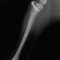

■ 症例20 ポメラニアン 8ヶ月 1.8kg

左右膝蓋骨脱臼 グレードⅢ

2ヶ月前から間欠的跛行が認められ、両膝の膝蓋骨脱臼整復術を行った。

手技は縫工筋及び内側広筋の解放、脛骨粗面の外側転位、滑車ブロック形造溝術、内外側関節包の縫縮を選択し実施した。

右側の膝蓋骨脱臼は上記手技で整復されたものの、左側はそれのみでは膝蓋骨が浮く様子が認められた。その為、PDS縫合糸にて膝蓋靱帯を1糸のみ縫合し、靱帯の縫縮を行った。

膝蓋骨脱臼は膝関節における膝蓋骨の内外側の脱臼と定義されるが、時として単純な内外の脱臼ではなく、膝蓋骨が大きく前方に浮き上がるように脱臼する場合がある。特にトイプードルやポメラニアンといった犬種に多く認められる。

内側脱臼に加えて前方への浮き上がりを矯正する為に、従来より脛骨粗面転移により膝蓋靭帯を外方と下方に引っ張り、固定する方法を選択する。膝蓋骨の前方への浮き上がりが軽度の場合は、従来法ではなく関節包の縫縮で対応していた。しかし、一部の症例で膝蓋骨の動きが悪くなり伸展機構が円滑に機能せずロボット様歩行になるケースがあった。

その為、膝蓋靭帯自体を縫縮する方法を採用した。この方法により、膝関節の伸展機構を妨げず膝蓋骨の軽度の浮きを矯正することが可能となった。

本症例の経過は良好である